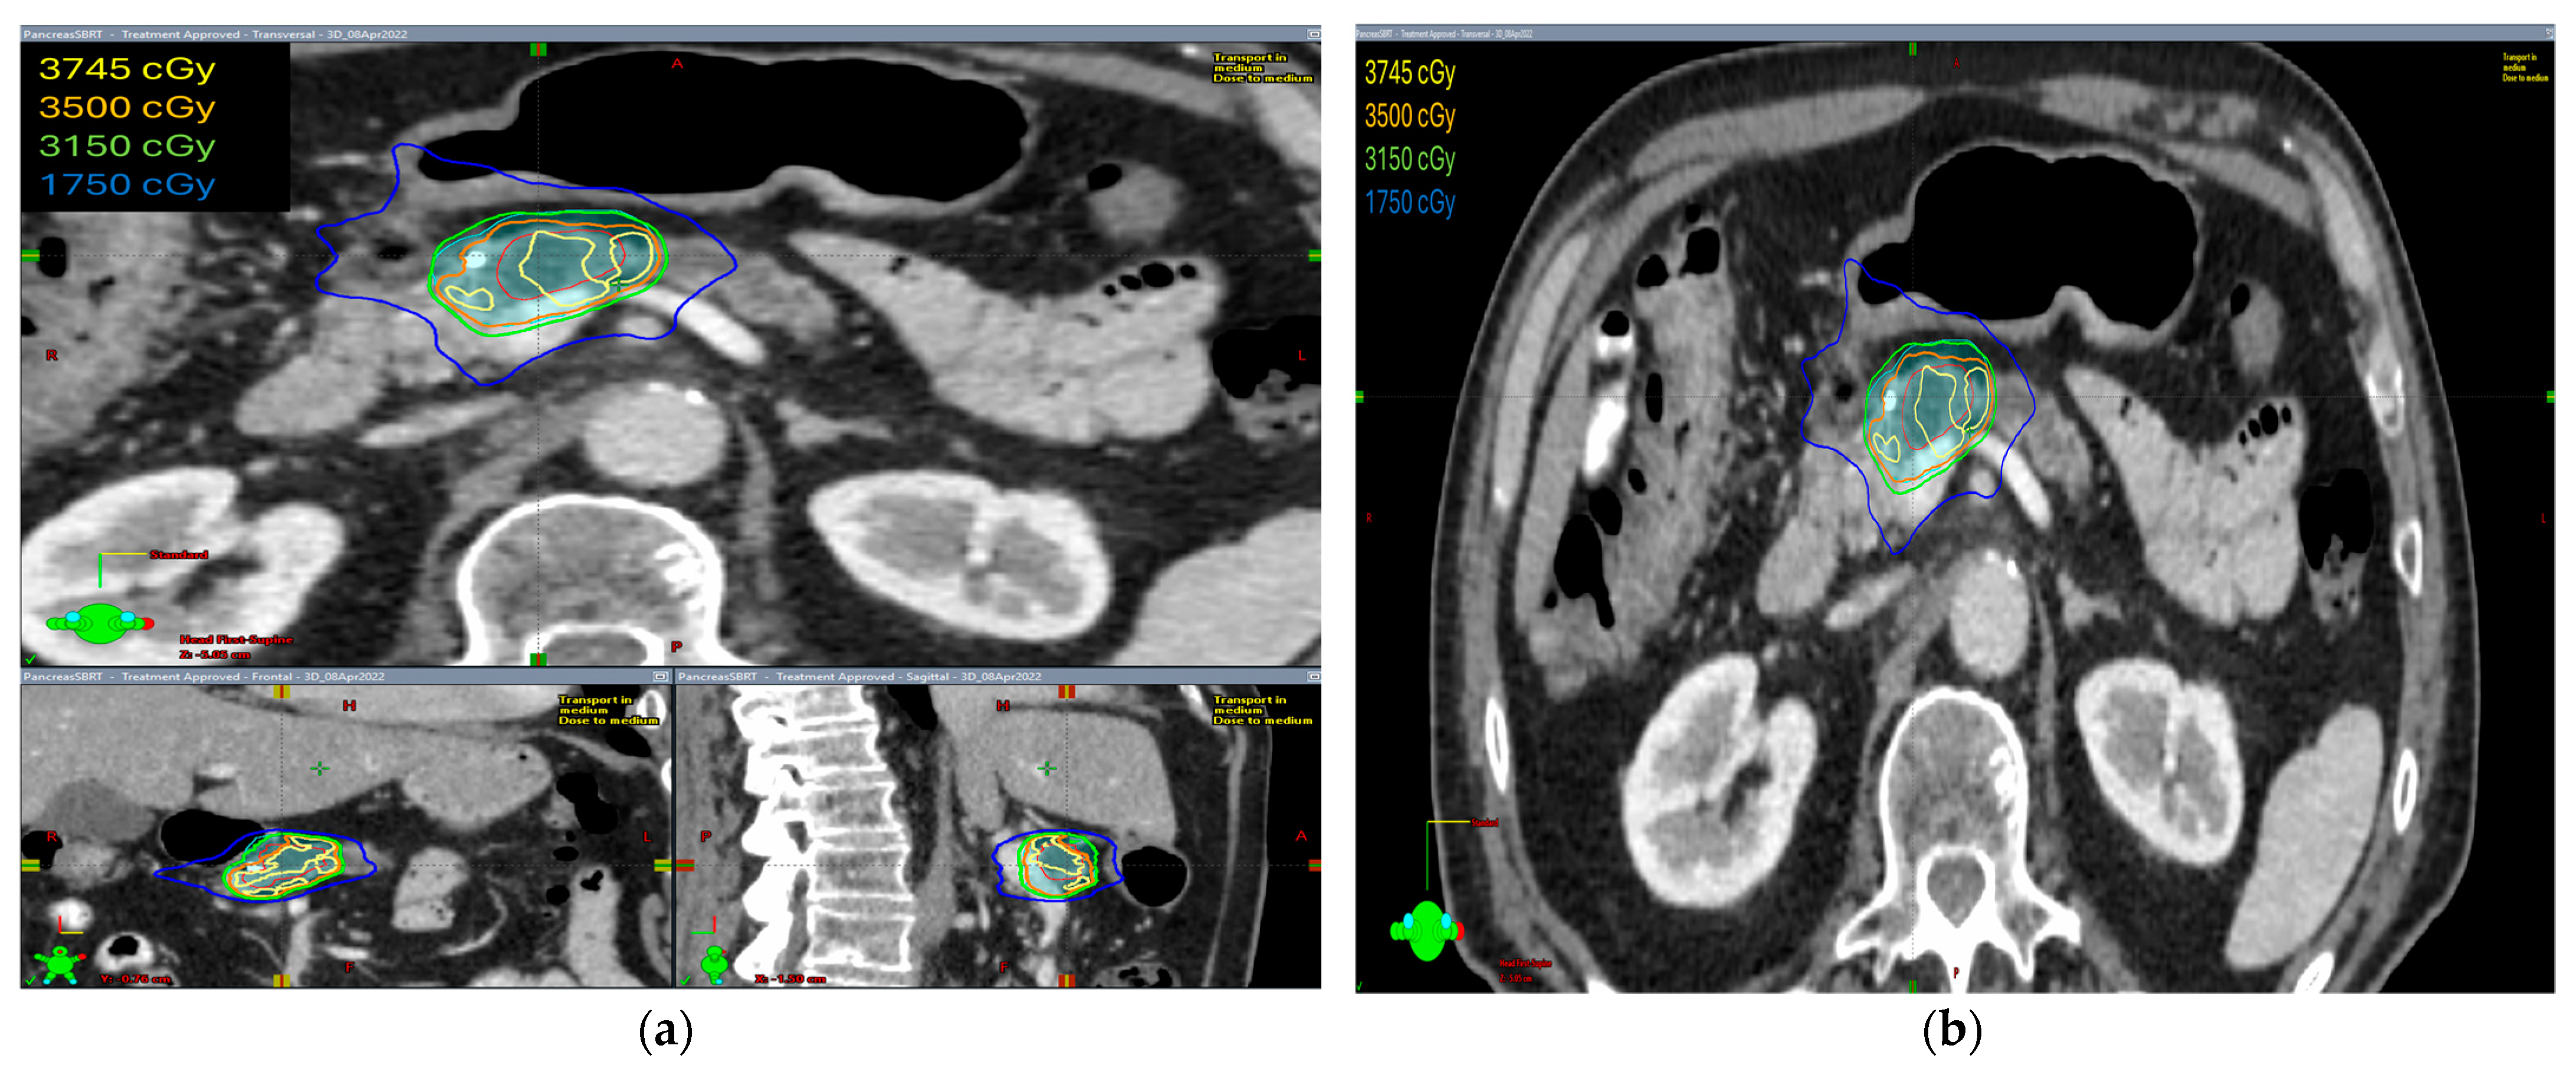

The radiation prescription dose was 35 Gy in five fractions in ten patients (58.8%). In five patients, the dose prescription was reduced to 30–33 Gy in five fractions and two patients received 40–50 Gy in five fractions. Median GTV volume was 28.60 cc (range 4.9–145.8 cc), median ITV was 29.15 cc (range 5.0–149.7 cc), and median PTV was 75.1 cc (range 19.9–255.3 cc). The isodose distribution for both abdominal compression and breath-hold technique is shown in Figure 1 and Figure 2, respectively.

The isodose distribution curves for target coverage and normal tissue dosing were evaluated. We found that the ITV was generated only in patients with abdominal compression to encompass the internal organ motion during treatment. Hence, PTV volumes were larger in these patients as compared with patients treated with breath-hold in which no ITV was drawn and smaller PTV volumes were irradiated.

Figure 1. The isodose distribution using abdominal compression technique (a) axial, coronal, and sagittal views (b) axial view.